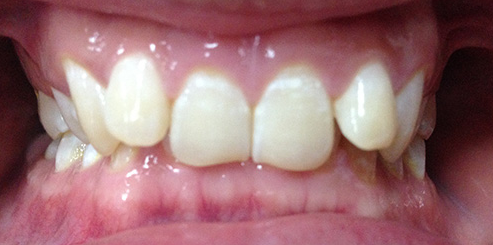

我们把牙齿在咬牙时,下牙被上牙全部盖住,或只露出很少的一部分,则可以判断为深覆合。

深覆合正面